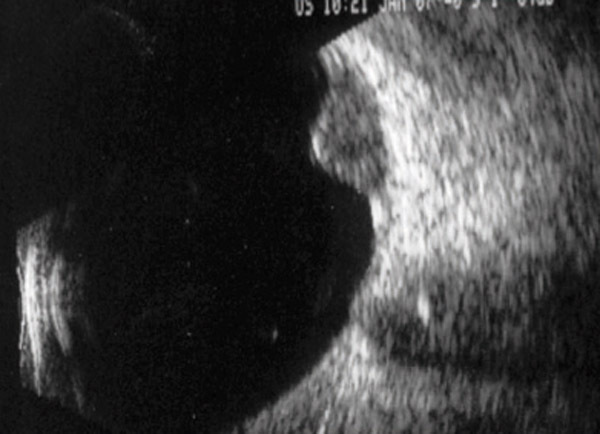

Masse choroïdienne saillante visible par échographie oculaire.